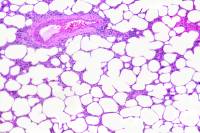

L'histologie animale est la science qui étude les structures microscopiques des animaux et de l'Homme, et tout particulièrement celles des cellules et des tissus biologiques qui constituent les organes.

Dans cette première partie de l'histologie des animaux, les tissus sont regroupés par appareil (ou système). L'étude de certains types de tissus et cellules animales, telles que l'on peut les observer au microscope optique, est réalisée dans une rubrique spécifique.